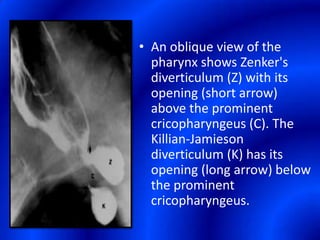

This document provides information about a barium swallow procedure. It begins with an introduction and overview of the embryology and anatomy of the pharynx and esophagus. It then describes the procedure itself, including preparation, technique, views obtained, and indications. Specific conditions that may be examined include pharyngeal and esophageal webs, foreign body impaction, scleroderma, dysphagia, mediastinal masses, and carcinoma. Diagrams are provided to illustrate normal anatomy and various pathological findings.